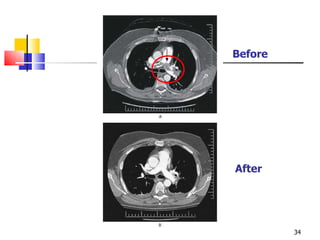

Before After

Tomographic scan showinginfarcted left lung, large clot in right main pulmonary artery

• #36 Figure 21-30. A, Computed tomographic scan demonstrating infarcted lung on left and large clot in the right main pulmonary artery. B, Autopsy specimen from same patient demonstrating organized clot in right main pulmonary artery. The patient presented with chronic dyspnea and hemoptysis and later died from complications of severe pulmonary hypertension. Patients with moderate to severe pulmonary hypertension may be considered for thromboendarterectomy. The operative mortality has decreased to approximately 5% with improvement in technique. Patients may experience dramatic relief of symptoms. Life-long anticoagulation is required to prevent recurrence.